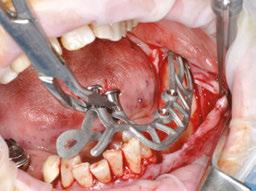

The procedure begins with local anesthesia at multiple points, vestibular and lingual, from the symphyseal region to the ascending ramus. However, an infiltration in the lingula of the mandible is not necessary. The incision is performed using the technique described above (Figures 5A and 5B).

It is imperative to carefully reflect a full-thickness flap following the periosteum. After reflection, an atraumatic periosteal expansion using a soft brush (Figure 6) will allow for the flaps to be repositioned without tension over the implant and bony surfaces at the end of the procedure.

Figures 8A-8D: Placing the subperiosteal implant and monitoring its adaptation Figures 5A and 5B: 5A. Initial clinical view. 5B. Access flap Figure 6: Periosteal expansion using a soft brush Figure 7: Prehension of the subperiosteal implant

After the soft tissue is prepared, the bony surface is carefully cleaned. For easy insertion, the healing abutments are left in place, and the implant is held firmly with hemostatic forceps (Figure 7). The implant is inserted via distal translation in the direction of the angle of the mandible, then a mesio-anterior rotation. The surgeon must control the lack of mobility and the adaptation of the implant to the bony surface at all points (Figures 8A, 8B, 8C, and 8D).

To ensure the implant is stable during the osseointegration period, an osteosynthesis screw is placed in the prepared space (Figures 9A, 9B, 9C, and 9D).

The flaps are carefully repositioned and sutured without tension with Halsted and over-and-over sutures (Figures 10A and 10B).